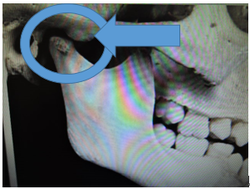

この写真の顎関節は小学校5,6年の形です。

顎関節の前方部の隆起が毎月、毎月成長していきます。

この為に、下顎骨を前方に適応させることが難しくなり上顎前突(出っ歯)の症状が突然目立ってきます。

この時期に矯正歯科医院を受診される人が増えてきます。

当矯正歯科医院ではこの時期に永久歯が萌え揃っていれば、治療を開始します。

この為に下顎骨を前方に適応させることが難しくなり、上顎前突(出っ歯)の症状が突然目立ってきます。

当矯正歯科医院ではこの時期に永久歯が萌え揃っていれば治療を開始します。

小学校5,6年

小学校2,3年